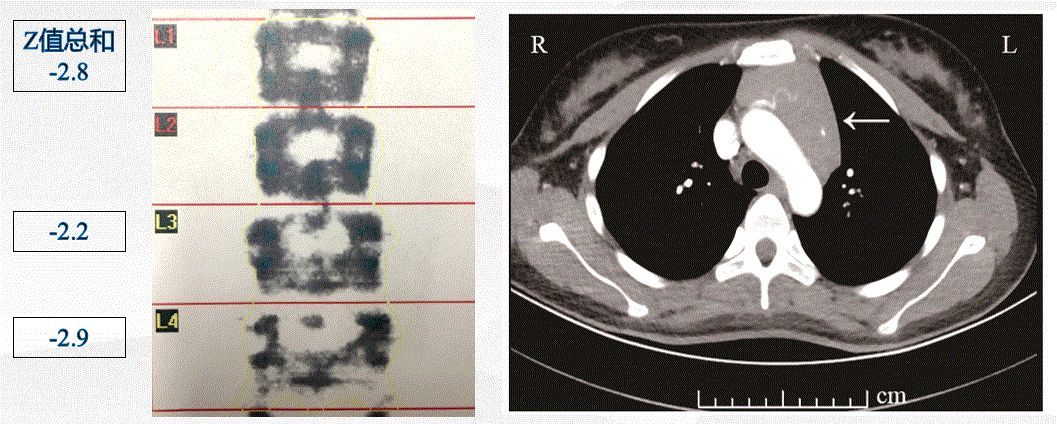

01 病情回顾 患者,女性,22岁。因“怕热、多汗、心悸1月余”入院。1月余前当地医院经甲状腺功能、甲状腺抗体和甲状腺超声等检查,明确诊断患者为“Graves病”,服药前患者肝功能轻度异常,未予保肝治疗。给予甲巯咪唑?10mg?qd、美托洛尔缓释片 47.5mg?qd治疗,4日后复查肝功能提示转氨酶明显增高,肝损较前明显加重,当地医院予停甲巯咪唑和美托洛尔缓释片,同时给予口服保肝药物治疗,另外予普萘洛尔?10mg?tid?控制心率。因肝损严重,当地医院建议同位素碘治疗Graves病甲亢。 因为患者甲状腺功能指标中的游离T3(FT3)和游离T4(FT4)均明显增高,大于正常值上限,核医学科考虑患者甲亢病情重,同位素碘治疗有风险,建议先内分泌科治疗,待甲亢病情稳定后再考虑同位素碘治疗。故将患者收入上海市第六人民医院内分泌科特需病房进一步治疗。 02 病情变化 身高 166cm,体重 56.1kg,P 105次/分,BP 111/66mmHg,BMI 20.36kg/m2。全身皮肤无潮湿,轻度突眼,眼球活动自如,无瞬目减少,辐辏反射正常,气管位置居中,甲状腺2度肿大,质韧偏软,活动度好,无压痛,未触及结节,甲状腺部位无震颤,无血管杂音,双手水平细颤阳性。 既往病史无特殊,近2月月经量少,周期正常。 入院后进行了详细的实验室及器械检查,根据检查结果,Graves病诊断比较明确,肝功能和中性粒细胞基本都正常。入院后甲状腺及颈部淋巴结超声的结果如下: 根据患者的检查结果,调整保肝药物继续保肝治疗,同时给予甲巯咪唑 15mg qd 治疗,普萘洛尔剂量加大,改为 20mg?tid。患者服药后心慌症状缓解,入院后第5天查房时患者主诉有较明显的恶心,时有呕吐。当时我们考虑患者是否服用甲巯咪唑后又出现了严重的肝功能损害,给予急查血常规、肝肾功能和血电解质,同时暂停服用甲巯咪唑。 检查结果出来后,出乎我们的意料,患者的血常规、肝肾功能均正常。但出现了较严重的高钙血症。结果如下: 患者入院时常规血电解质检测,血钙轻度增高为2.65 mmol/L,当时考虑甲亢本身会引起高钙血症且血钙轻度增高,故未予特殊处理。但是根据最新的检查结果,血钙明显增高,考虑患者恶心、呕吐等消化道症状应该是高钙血症导致的,与肝功能损伤没有关系,故继续甲巯咪唑服用,剂量不变,仍为 15mg qd,同时给予补液水化等降血钙治疗。 高钙血症最常见的原因主要是甲状旁腺功能亢进和恶性肿瘤。故针对高钙的原因又补充了一系列检查,发现患者甲状旁腺激素明显降低,尿钙排出明显增高,结果如下: 因为甲状旁腺激素明显降低,考虑是高钙引起的甲状旁腺激素抑制,而且甲状旁腺扫描(甲状旁腺ECT)也未发现甲状旁腺部位、纵隔区及其他部位放射性浓聚。故原发性甲状旁腺功能亢进症基本排除。甲状旁腺扫描结果如下: 因为排除了原发性甲旁亢,故我们后续的检查主要聚焦于恶性肿瘤的排查。但肿瘤标记物、骨髓穿刺、血清免疫固定电泳均正常;全身骨显像也未见明显异常。 但在检查过程中,发现了两个明显异常的检查结果:严重骨质疏松和胸腺明显增大。因为患者年龄仅22岁,所以目前的骨密度对于患者来说是相当低的,部分骨代谢指标检测结果如下:骨钙素 51.46ng/mL?增高(正常范围 11-46);B-胶原特殊序列 (βCTX) 2105.00 ng/L?增高(正常范围 < 573)此外,根据胸部CT图像,我们初步计算了胸腺的体积,根据相应的公式,胸腺体积达到?1963.58mm2。相应结果如下: 根据检查结果,我们当时高度怀疑胸腺增生是否与高钙血症和骨质疏松有关,因为有文献报道,胸腺本身可以分泌PTH相关肽(Parathyroid?hormone-related?peptide,?PTHrP)?引起骨吸收增加而出现高钙血症和骨质疏松,因此我们曾打算给患者行胸腺穿刺以明确诊断,必要时考虑胸腺切除手术治疗。 但是考虑到患者甲亢未完全控制,而且也无法确定胸腺增生与高钙是否一定相关,另外,经过补液水化等治疗,患者的血钙水平也已经下降;最后,Graves病本身也有引起胸腺增生的可能,故暂缓胸腺穿刺。继续予甲巯咪唑 15mg qd 治疗甲亢、保肝药物保肝治疗,密切监测电解质,嘱患者出院后定期随访观察。出院时血钙明显下降,基本接近正常,结果如下: 甲亢治疗4周后患者甲功有所改善,血钙恢复至正常范围。继续给予抗甲状腺药物治疗,患者甲状腺激素和TRAb水平逐渐下降;PTH也逐渐上升至正常范围;血钙和血磷水平保持在正常范围。后续治疗过程中保肝药物也逐渐减量,最后停用。 患者甲亢治疗8月后,患者骨密度有改善,L1-4骨密度-2.4g/cm2,颈部骨密度-0.7g/cm2。让我们意外且欣喜的是,患者复查胸部CT显示明显肿大的胸腺已经明显缩小,经过公式计算,胸腺体积已经缩小至?911.01mm2,治疗前后的CT结果比较如下: 甲亢治疗14个月后,患者复查甲状腺功能、TRAb、骨代谢指标及骨密度结果如下:? 在整个治疗过程中,甲亢控制后,患者血钙一直保持在正常范围内。 目前患者还一直在糖甲大院李医生这里随访,目前服用甲巯咪唑 5mg qd 控制甲亢,甲状腺功能指标一直控制在比较理想的范围内,TRAb也已经恢复正常,但最近本院刚开展的检测项目-促甲状腺激素受体刺激性抗体(TSAb)还稍微偏高,结果如下: 03 病情分析 根据入院后一系列检查,Graves病甲亢、药物性肝功能损害诊断明确。但巨大胸腺增生、明显高钙血症、严重骨质疏松大尤其是胸腺增大的原因当时无法明确。甲亢可以引起高钙血症、骨质疏松及胸腺增生,但巨大的胸腺增生很罕见。这三者间是不是存在某种联系?会不会增大的胸腺分泌某些物质引起高钙血症和骨质疏松?查阅文献,胸腺确实会分泌PTH相关肽而引起高钙血症。当时我们也怀疑巨大的胸腺是不是高钙血症的原因,也打算是否考虑胸腺穿刺活检以明确胸腺病变。 我们在随访观察中,发现随着甲亢的好转,患者血钙降至正常,而且治疗过程中FT3及FT4水平与血钙呈显著正相关,提示甲亢是导致高钙发生的原因,结果如下: 另外,甲亢治疗控制后患者的骨质疏松、胸腺增大均明显好转,也提示甲亢是导致患者骨质疏松和胸腺增大的根本原因。至此,经过长时间的随访观察,通过甲亢治疗后患者高钙血症消失、骨质疏松缓解、胸腺增生明显缩小,推断甲亢是引起这一系列症状的根源。 04 可能机制 据报道,大约20%的甲状腺功能亢进症患者可能伴轻度至中度的高钙血症。极少数甲亢患者可能会出现高钙危象。甲亢时甲状腺分泌过多的甲状腺激素,甲状腺激素对钙磷代谢有双重作用。一方面,甲状腺激素可以抑制甲亢患者体内活性维生素D的水平,肠道和肾脏对钙和磷的吸收降低,而肾脏对钙和磷的排泄又增加。另一方面,甲状腺激素可以加速骨转化,特别是破骨细胞活性增加,从而导致血钙水平的增高。 本病例罕见之处在于:明显高钙血症、严重骨质疏松和巨大胸腺增生同时发生于Graves病甲亢患者。病例给我们的启发很多,临床医生在诊断治疗临床常见疾病时不可忽视常见疾病少见症状的存在及处理,否则可能造成漏诊和误诊,短时间内无法明确诊断时,在病情允许的情况下随访观察病情变化也许是一个比较明智的解决办法。 最后,糖甲大院李医生还是要和各位分享一下自己的心得体会。 ?Yan D, Xu Y, Li LX.The coexistence of hypercalcemia, osteoporosis and thymic enlargement ingraves' disease: a case report. BMC Endocr Disord. 2020.?20(1): 97. Medas F, Erdas E, Loi G, et al. Intraoperative parathyroid hormone (PTH) testing in patients with primary hyperparathyroidism and PTH levels in the normal range. BMC Surg. 2019;18(Suppl 1):124. Williams GR, Bassett JHD. Thyroid diseases and bone health. J Endocrinol?Investig. 2018;41(1):99–109. Ryan CS, Petkov VI, Adler RA. Osteoporosis in men: the value of laboratory?testing. Osteoporos Int. 2011;22(6):1845–53. Gunn A, Michie W, Irvine WJ. The Thymus in Thyroid Disease. Lancet. 1964;?2(7363):776–8. Dalla Costa M, Mangano FA, Betterle C. Thymic hyperplasia in patients?with?Graves' disease. J Endocrinol Investig. 2014;37(12):1175–9. Gessi M, Monego G, Lauriola L, Maggiano N, Ranelletti FO. Parathyroid hormone-related peptide (hPTHrP) and parathyroid hormone-related peptide receptor type 1 (PTHR1) expression in human thymus. J Histochem Cytochem. 2005;53(8):955–62.